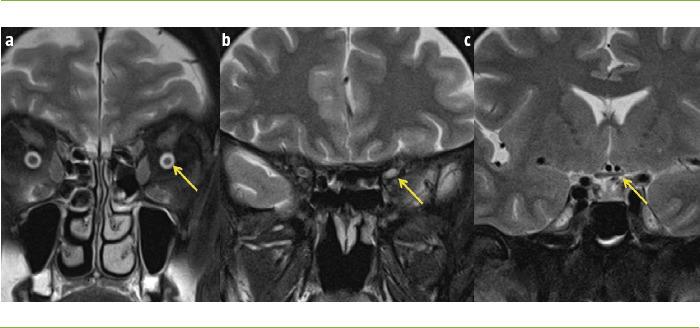

The main causes of optic neuritis (ON) are multiple sclerosis (MS), neuromyelitis optica spectrum disorder (NMOSD) and myelin oligodendrocyte glycoprotein antibody disease, also known as MOGAD. When all screening is negative, we can speak of idiopathic ON, although this diagnosis should be provisional. ON can be diagnosed clinically and paraclinical tests are not routinely required to confirm it. However, tests such as magnetic resonance imaging (MRI), visual evoked potentials (VEP) and optical coherence tomography (OCT) can lend support to the diagnosis if the clinical presentation is atypical. The use of new MRI sequences, OCT, multifocal VEPs and the determination of neurofilaments has allowed ON to be used as a model for remyelination and neuroprotection, leading to phase II clinical trials. Some of these drugs, such as opicinumab, clemastine, phenytoin or simvastatin, have shown positive results; however, their clinical effect remains to be defined. It is accepted that corticosteroids do not improve the long-term prognosis of ON, although some retrospective studies suggest that there is a therapeutic window from the onset of symptoms. Plasmapheresis has also been shown to be effective in patients with ON. In this review we will address basic aspects of the management of ON, in the fundamental context of MS, NMOSD and MOGAD, with emphasis on etiopathogenic, diagnostic, prognostic and therapeutic developments.

视神经炎(ON)的主要病因包括多发性硬化症(MS)、视神经脊髓炎谱系障碍(NMOSD)以及髓鞘少突胶质细胞糖蛋白抗体病,也称为MOGAD。当所有筛查均为阴性时,我们可以称之为特发性ON,不过这一诊断应为临时性的。ON可通过临床诊断,通常无需辅助检查来确诊。然而,如果临床表现不典型,诸如磁共振成像(MRI)、视觉诱发电位(VEP)和光学相干断层扫描(OCT)等检查可为诊断提供支持。新型MRI序列、OCT、多焦VEP的应用以及神经丝的测定已使ON能够作为再髓鞘化和神经保护的模型,从而开展II期临床试验。其中一些药物,如opicinumab、氯马斯汀、苯妥英或辛伐他汀,已显示出阳性结果;然而,它们的临床效果仍有待确定。尽管一些回顾性研究表明从症状出现开始存在一个治疗窗口期,但普遍认为皮质类固醇并不能改善ON的长期预后。血浆置换在ON患者中也已显示出有效性。在本综述中,我们将探讨在MS、NMOSD和MOGAD的基本背景下ON管理的基本方面,重点关注病因、诊断、预后和治疗进展。